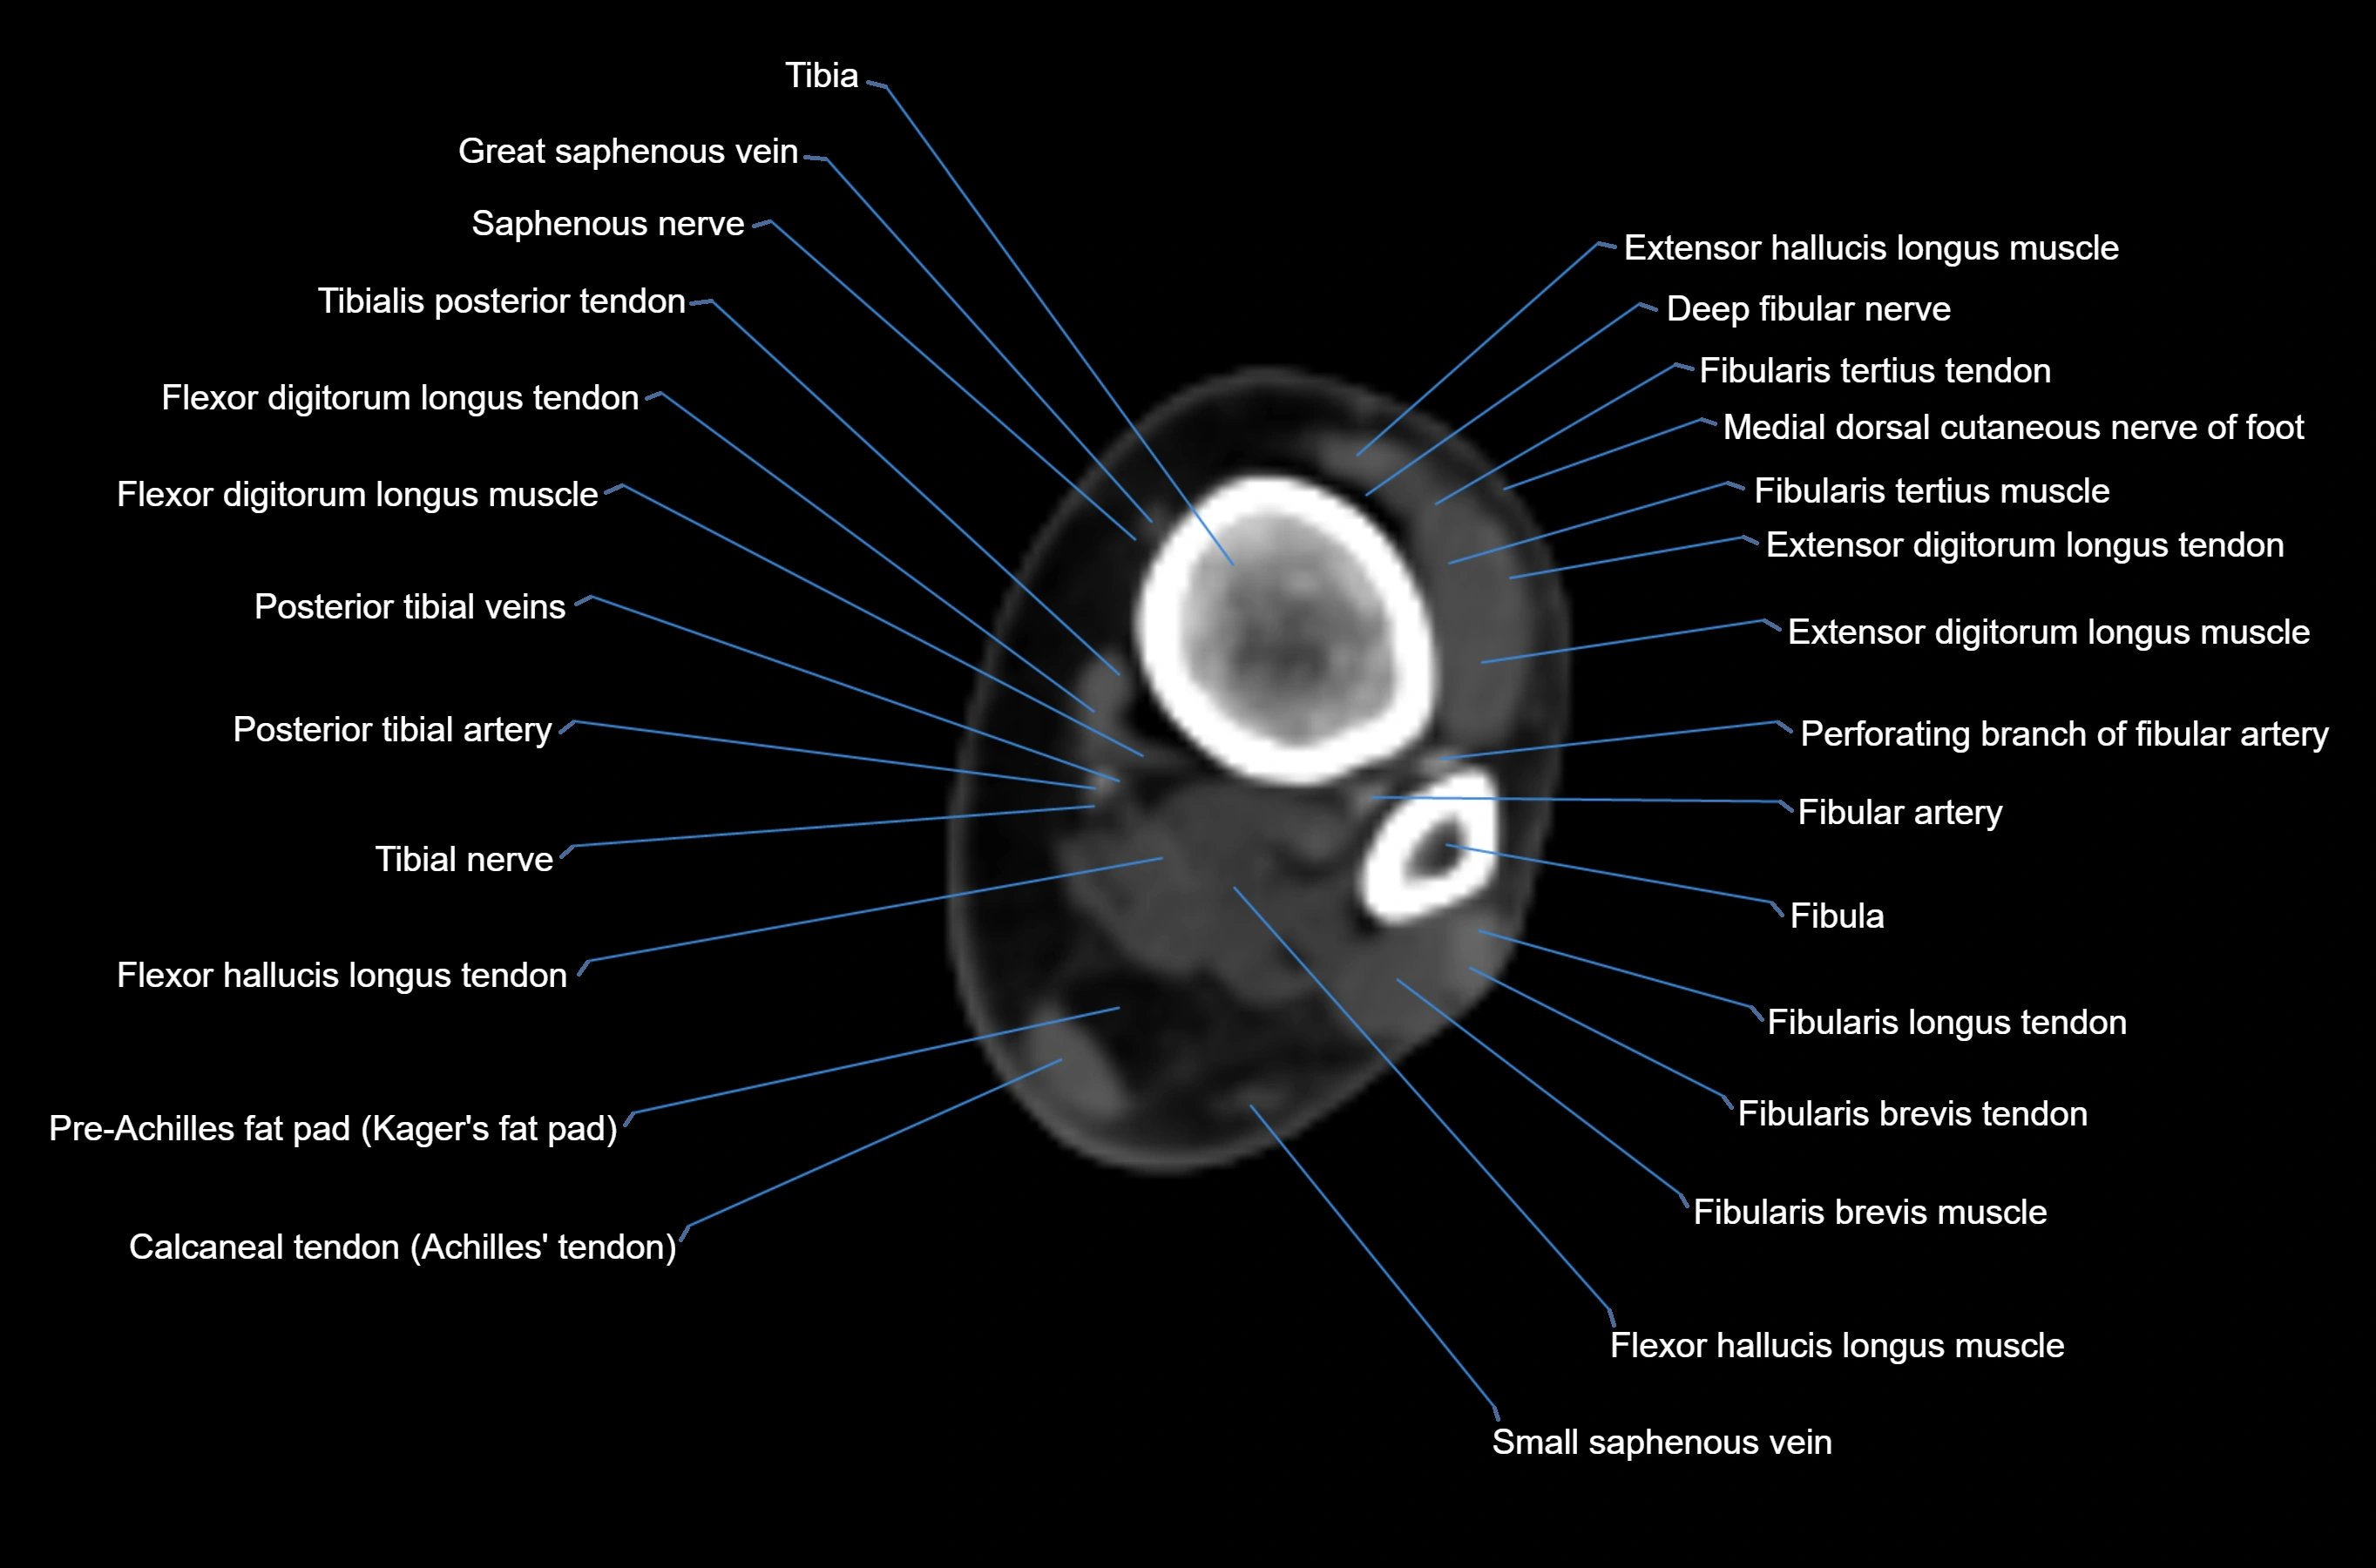

- Fibula

- Fibular artery

- Fibularis brevis muscle

- Fibularis brevis tendon

- Fibularis longus muscle (peroneus longus muscle)

- Fibularis longus tendon

- Fibularis tertius muscle

- Fibularis tertius tendon

- Flexor digitorum longus muscle

- Flexor digitorum longus tendon

- Flexor hallucis longus muscle

- Flexor hallucis longus tendon

- Kager fat pad (pre-Achilles fat pad)

- Posterior tibial artery

- Posterior tibial veins

- Saphenous nerve

- Small saphenous vein

- Tibia

- Tibial nerve

- Tibialis posterior tendon